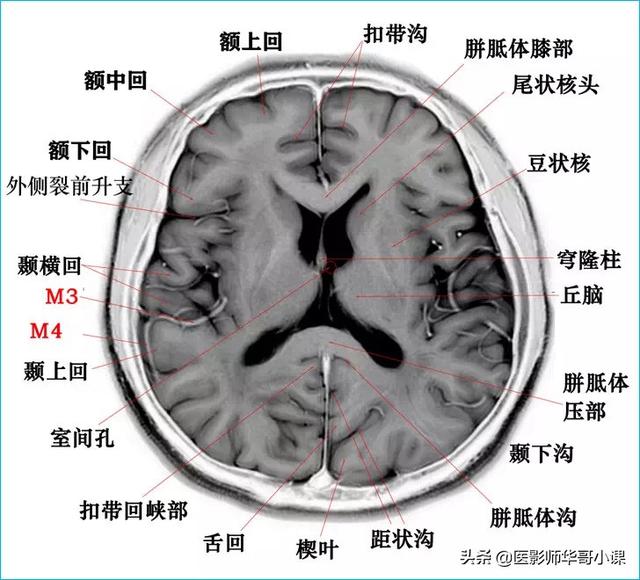

颅脑主要包括大脑、小脑、脑干、间脑,其中大脑又称为端脑,是人体的司令部,管辖人体的躯体活动、精神活动以及感觉行为等;脑干和小脑位于后颅窝的位置,脑干自上而下分为中脑、脑桥、延髓,脑干又称为生命中枢,对人体非常重要,因为脑干具有管辖呼吸和循环的初级生命中枢。其中大脑分为5个脑叶,分别是额叶、顶叶、颞叶、枕叶以及内侧面的岛叶。间脑分为上丘脑、下丘脑、后丘脑、背侧丘脑和底丘脑,背侧丘脑是一个重要的结构,是感觉传导路的重要中继站。颅脑包括颅骨和颅骨内的脑组织。颅骨由顶骨,颞骨,枕骨,额骨,以及颅底骨构成。颅骨构成的颅腔主要作用是保护脑组织。颅内的脑组织主要包括大脑,小脑,脑干。表面覆盖有软脑膜和硬脑膜,大脑分为左右两侧大脑半球,根据解剖位置又分为颞叶,枕叶,顶叶,额叶,各脑叶功能不尽相同。小脑也分左右半球。脑干分为延髓,脑桥和中脑三部分。

颅脑磁共振可提供冠状位、矢状位和横位三维的图像,图像清晰度高,对人体没有放射性的损害,尤其是可以清楚的显示脑干、小脑及后颅窝的病变,颅脑磁共振平扫可以用于诊断脑梗死、脑炎、脑肿瘤、颅脑先天发育畸形、颅脑外伤等。